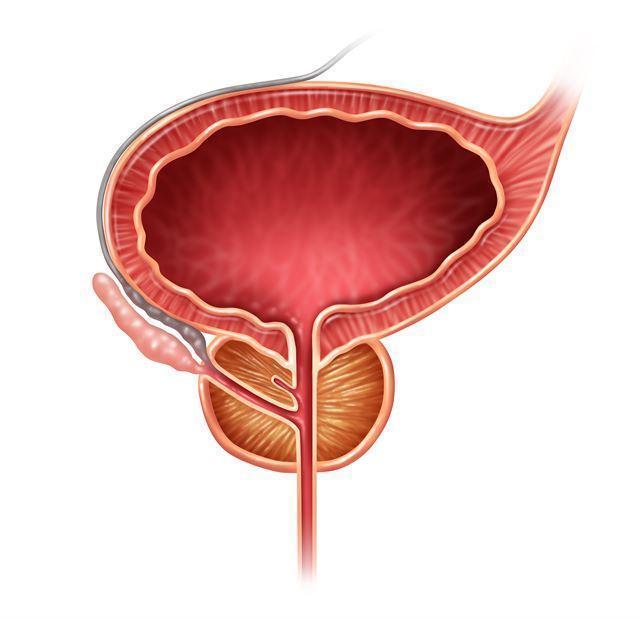

남성에게만 있는 전립선은 밤톨 모양이며 평균적으로 호두 크기 정도라고 합니다. 길이는 다양하지만 약 4cm 정도이며 방광과 요도 사이의 골반 깊숙한 곳에 위치합니다. 전립선이 하는 일은 매우 기본적인 배뇨와 정액이 나오는 방식입니다. 전립선과 관련된 질병에는 전립선암과 전립선 비대가 있습니다.

전립선은 정액의 일부를 생성하는 남성 고유의 기관입니다. 전립선은 방광에서 나오는 입구인 요도를 둘러싸고 있으며 밤송이 모양을 하고 있습니다. 전립선은 정액의 일부를 생산하는 것 외에도 정자에 영양을 공급하고 운동성을 촉진하는 전립선액을 분비합니다.

전립선암은 전립선에 암세포가 발생하는 질환입니다. 전립선의 일부 세포가 정상 세포의 성장을 조절하는 능력을 상실하고 통제할 수 없을 정도로 성장하여 악성 종양이 되는 질환입니다. 일반적으로 전립선암은 주로 전립선 상피 세포에서 발생하는 선암으로, 약 70~80%가 전립선 말초 부위에서 발생합니다.